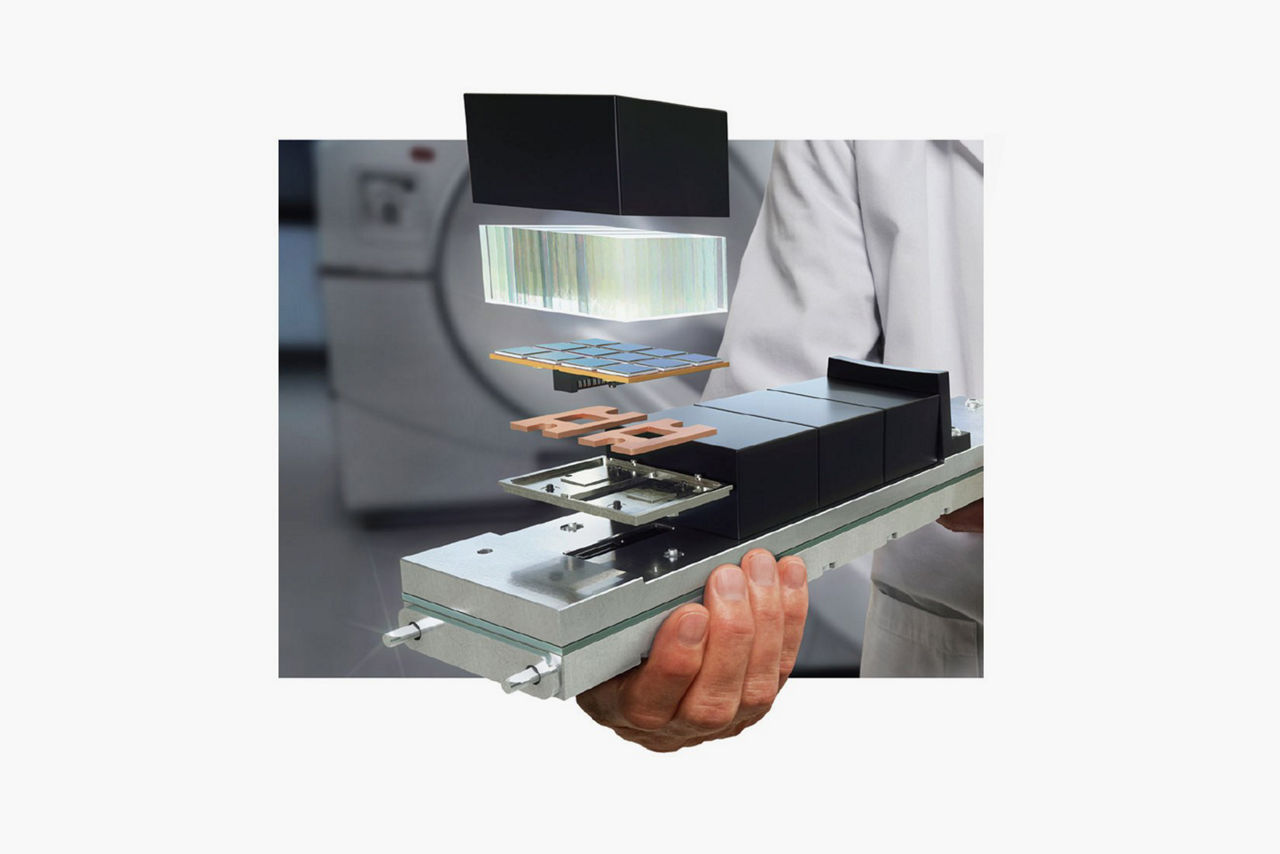

The LightBurst Digital Detector is a key component of what made Discovery MI the leading digital PET system. This innovative digital PET detector technology combines a small lutetium-based scintillator crystal array with a Silicon Photomultiplier (SiPM) block design for significant improvements in sensitivity, scan times, and required dose levels compared to similar ToF technology. Discovery MI Gen 2 provides next-level digital detection with an axial FOV scalable up to 30 centimeters and the corresponding potential to reach even greater levels of sensitivity.